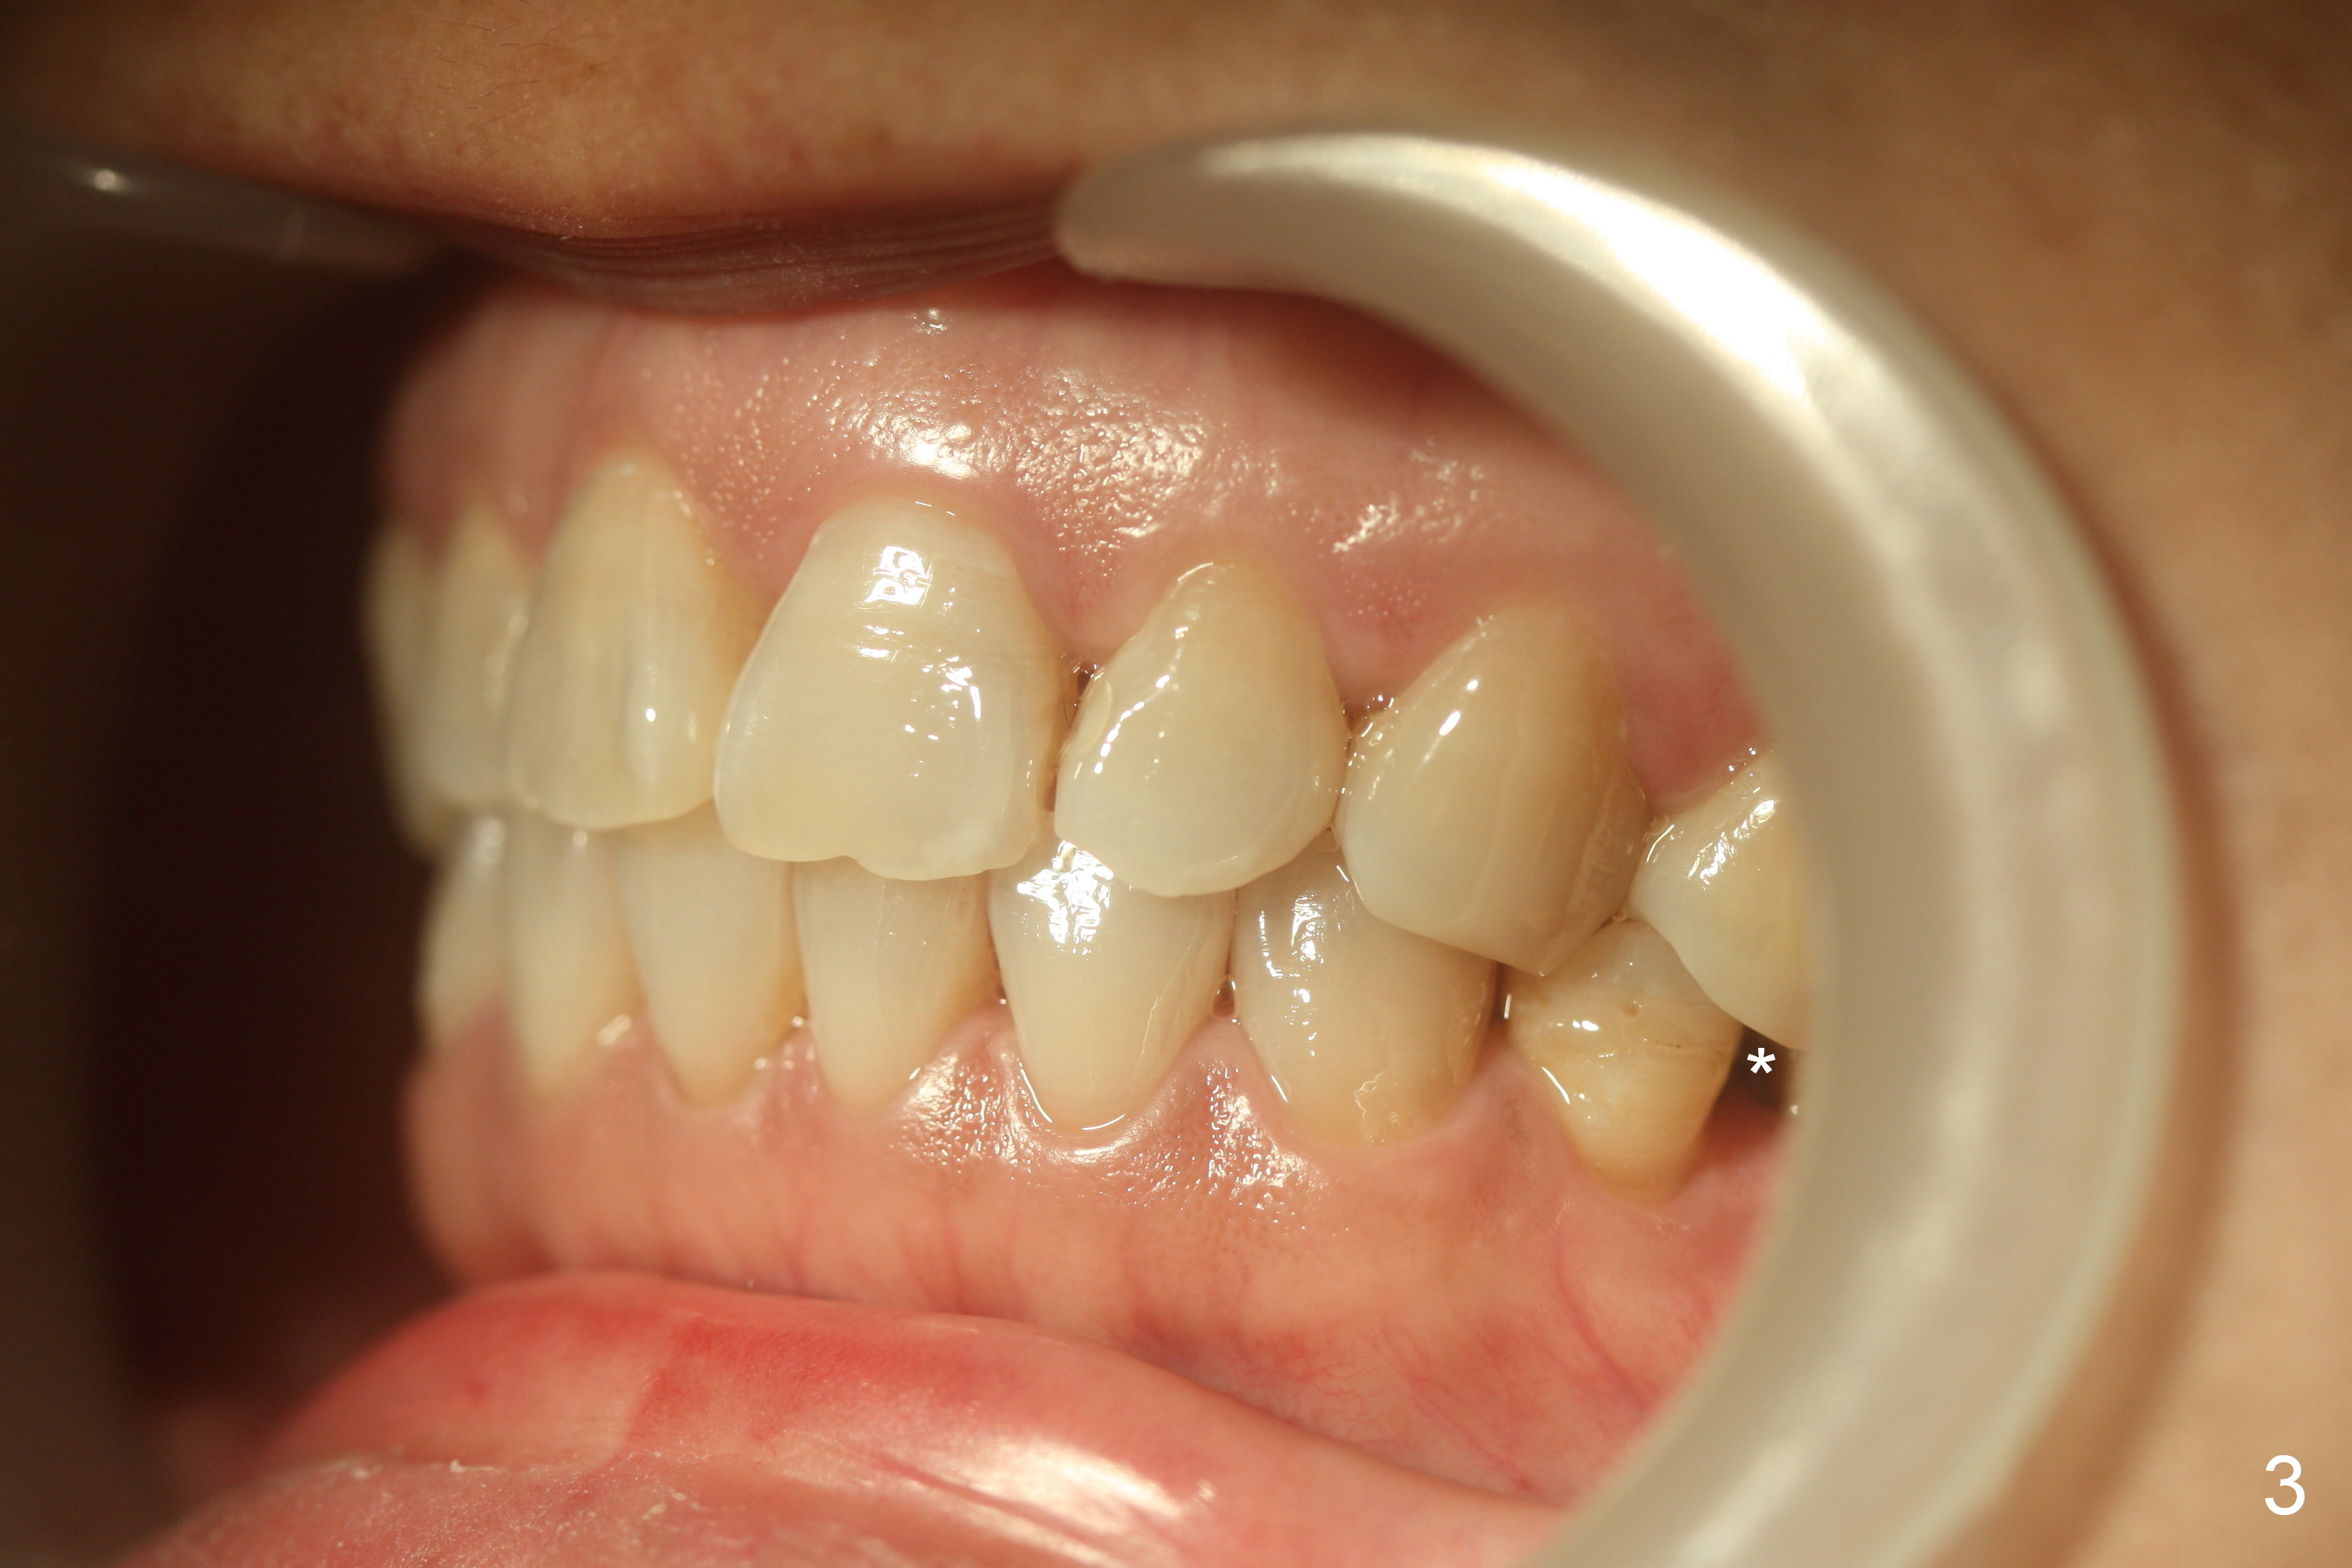

Show the patient that the tooth #31 is severely mesially tilted with reduction in the mesiodistal width for implant placement (Fig.5,7). The tooth #32 is severely malpositioned (linguoversion, Fig.6). It is extremely difficult to gain space for the implant without #32 extraction.

Four weeks of using open coil spring between #29 and 31, these teeth seem to have rotated (Fig.8,9 curved arrows). After placing a longer spring and the same arch wire, power chains are installed to close the anterior diastema (Fig.10 ^). The patient notes the divergence between #20 and 21 (Fig.11). To correct the latter, either place #20 bracket more distal (Fig.11 *) or place power chains between these teeth only. To facilitate #31 distalization (Fig.13), place lingual buttons (Fig.12 red) in the mesial surface of #31 and the distal of #2 with an elastic between the buttons.